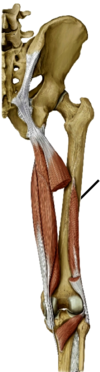

What is the muscle to the left of the line?

Semimembranosus (looks like a tendon)

- ischial tuberosity –> medial tenondon condyl fibers refelct back up to fossa and become oblique tendon

- tibial part of sciatic (L4-S3)

- extend hip, flex knee

hamstring muscle

Posterior thigh muscle

What muscle is this?

- What is its orgin and insertion?

- What is its innervation

- What is its actions?

Biceps Short head

- lateral lip of linea aspera–> ******head of fibula********

- common fibular part of scatitc (L4-S2)

- flex knee

- only one that does not extend the hip

Hamstring muscle

posterior thigh muscle